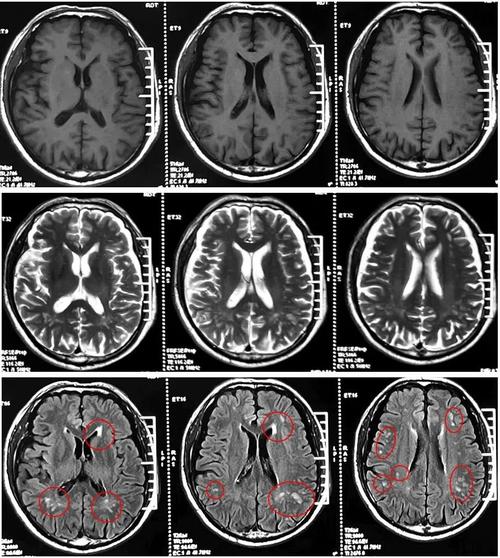

腔梗:

(图片来源网络,侵删)- 这是核心诊断。“腔隙性脑梗塞”的简称。

- 简单理解:可以把它想象成大脑里非常微小的“小中风”或“小梗塞”。

- 形成原因:我们的大脑里有非常细小的血管,叫做“穿通动脉”,这些血管为大脑深部的一些重要结构(如基底节、丘脑、脑干等)供血,当这些小血管因为各种原因(比如堵塞、变性)发生堵塞时,它所供应的那一小块脑组织就会因为缺血而坏死,形成一个微小的“洞”或“腔隙”,这个坏死区域就叫做“腔隙性脑梗塞”。

- 大小:通常病灶非常小,直径一般在1.5-3毫米左右,所以报告描述为“少许”,说明数量不多,且体积很小。